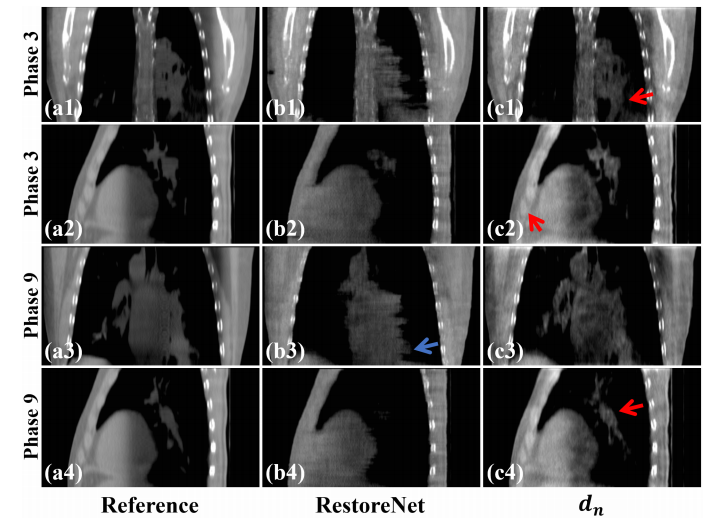

Fig. 13. Reconstructed results from Phases 3 and 9 on the simulated dataset. (a1)-(a4) Reference images reconstructed from full-sampled projections, (b1)-(b4) Images processed by RestoreNet, (c1)-(c4) Images provided by 𝑑𝑑𝑛𝑛. The display window is [0.004, 0.014] mm-1 .

图13. 在模拟数据集中,相位3和9的重建结果。(a1)-(a4) 从全采样投影重建的参考图像,(b1)-(b4) 由RestoreNet处理的图像,(c1)-(c4) 由DDNet提供的图像。显示窗口为 [0.004, 0.014] mm^-1。